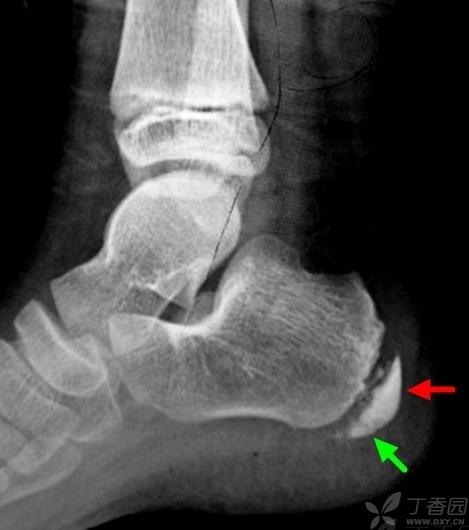

跟骨骨骺炎x线影像图

跟骨骨骺炎x线影像图,正常儿童跟骨骨骺图片

支持大家的意见:跟骨骨骺炎. 表现: 跟骨骨骺密度不均匀增高

儿童跟骨骨骺炎

儿童跟骨骨骺x线图片

跟骨骨骺炎

儿童跟骨骨骺炎x线

儿童跟骨骨骺炎图片

跟骨骨骺